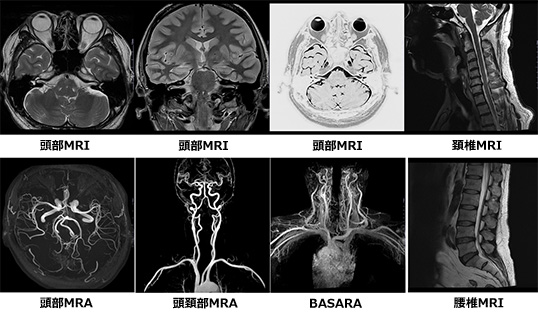

ドイツ シーメンス社製の最新鋭MRI装置「MAGNETOM Lumina」を導入しています。

AIを用いた画像再構成技術を使用することで、質の高い画像を提供することができ、高速撮影技術を用いてこれまでの装置よりも検査時間を短縮することが可能になりました。

また、従来よりボア経が約10cm広くなったことにより撮影時の圧迫感軽減ができるなど、患者さんにとって一番負担の少ない体勢を選択して検査を行うことができます。

Signa HDxt 1.5T

最新鋭器に更新することにより、これまで以上に高画質の撮影が可能となりました。また、これまでにはできなかった、新たな画像も撮影できるようになり、日常臨床に役立てています。